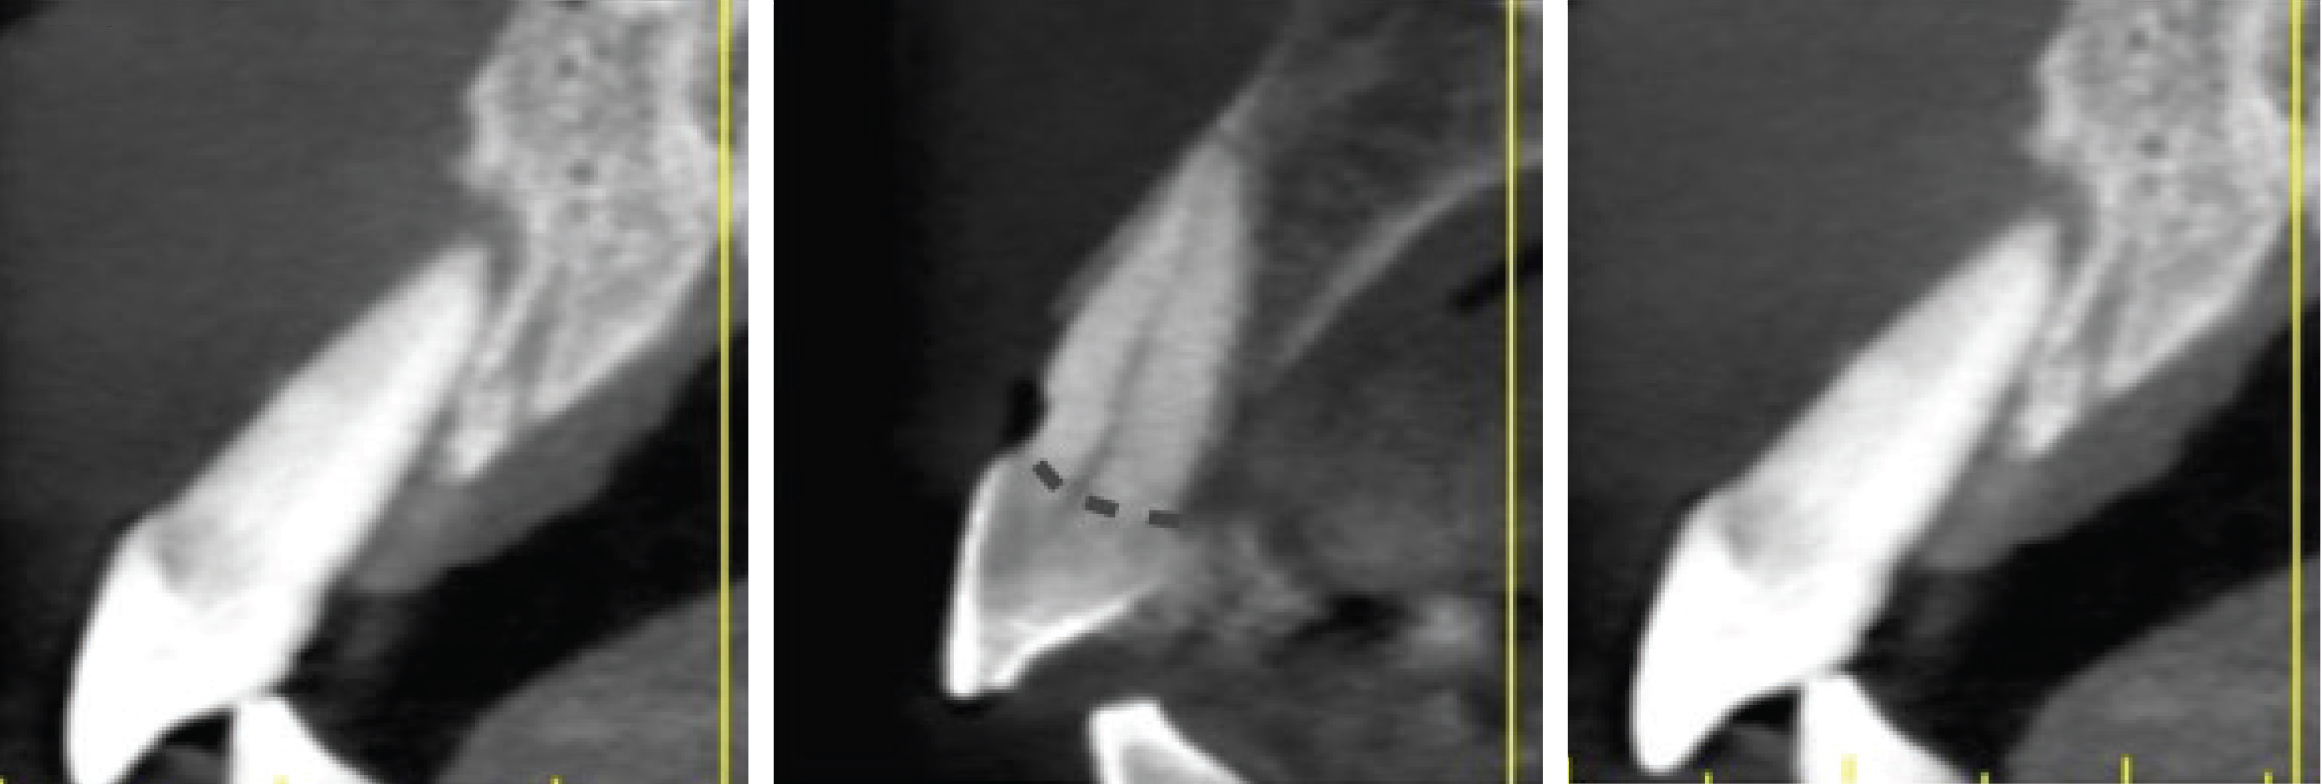

Imagery depicting examples of single-rooted sockets showing periodontium status, socket conditions, and CBCT imaging is presented in Figure 2 through Figure 5.

Grade I

Grade I sockets are the most ideal. Following tooth extraction, a socket that has an intact buccal plate, adequate interproximal bone, and satisfactory apical topography will fall into this category. In this classification, an intact buccal plate is defined as having no fissures or dehiscences and less than 25% loss of height (Figure 4, left; Figure 5, left). This percentage of buccal plate loss was selected as the cutoff based on the average root length of single-rooted teeth, which is 14.2 mm,25 and the amount of buccal plate that can be reliably regenerated during immediate implant placement. Adequate apical topography is defined as enough bone present apical to the extraction site to allow for engagement of 3 mm to 4 mm of a properly positioned immediate dental implant (Figure 2).1,2 Adequate interproximal bone is defined as no or mild (up to 2 mm) periodontal bone loss on the adjacent teeth as to allow for support of the interproximal soft tissue and to enable placement of the platform of an immediate implant in the proper apical-coronal position relative to the adjacent teeth while still being bordered by bony walls on the mesial and distal aspects26 (Figure 3, left).

Grade II

Grade II sockets are differentiated from Grade I by the amount and quality of the remaining buccal plate. A Grade II socket has a fissure, dehiscence, or deficiency of the buccal plate totaling a 25% to 50% loss. Like Grade I sockets, they have adequate interproximal bone and apical topography (Figure 3, left; Figure 4, center; Figure 5, center).

Grade III

Grade III sockets are the most deficient and include any socket with inadequate apical topography, insufficient interproximal bone, or more than 50% loss of buccal plate. Inadequate apical topography is defined as not enough bone present apical to the extraction site to allow for implant placement and may be the result of bone loss caused by periapical lesions or concavities due to existing anatomy of the alveolus (Figure 4, right; Figure 5, right). Insufficient interproximal bone is defined as moderate-to-severe periodontal bone loss—greater than 2 mm on one or both of the adjacent teeth.